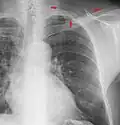

Landmarks

A chest radiograph with the angle parts of the ribs and some other landmarks labeled.

In the average person, the diaphragm should be intersected by the 5th to 7th anterior ribs at the mid-clavicular line, and 9 to 10 posterior ribs should be viewable on a normal PA inspiratory film. An increase in the number of viewable ribs implies hyperinflation, as can occur, for example, with obstructive lung disease or foreign body aspiration. A decrease implies hypoventilation, as can occur with restrictive lung disease, pleural effusions or atelectasis. Underexpansion can also cause interstitial markings due to parenchymal crowding, which can mimic the appearance of interstitial lung disease. Enlargement of the right descending pulmonary artery can indirectly reflect changes of pulmonary hypertension, with a size greater than 16 mm abnormal in men and 15 mm in women.[6]

Appropriate penetration of the film can be assessed by faint visualization of the thoracic spines and lung markings behind the heart. The right diaphragm is usually higher than the left, with the liver being situated beneath it in the abdomen. The minor fissure can sometimes be seen on the right as a thin horizontal line at the level of the fifth or sixth rib. Splaying of the carina can also suggest a tumor or process in the middle mediastinum or enlargement of the left atrium, with a normal angle of approximately 60 degrees. The right paratracheal stripe is also important to assess, as it can reflect a process in the posterior mediastinum, in particular the spine or paraspinal soft tissues; normally it should measure 3 mm or less. The left paratracheal stripe is more variable and only seen in 25% of normal patients on posteroanterior views.[7]

Localization of lesions or inflammatory and infectious processes can be difficult to discern on chest radiograph, but can be inferred by silhouetting and the hilum overlay sign with adjacent structures. If either hemidiaphragm is blurred, for example, this suggests the lesion to be from the corresponding lower lobe. If the right heart border is blurred, than the pathology is likely in the right middle lobe, though a cavum deformity can also blur the right heard border due to indentation of the adjacent sternum. If the left heart border is blurred, this implies a process at the lingula.[8]